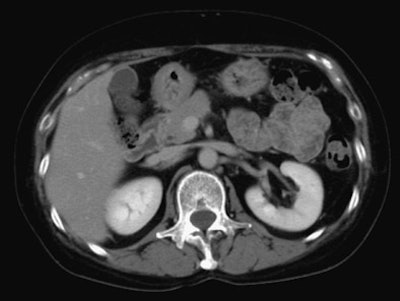

![]() |

| Above, 10-second delay (corticomedullary phase) seen in 46-year-old male patient. |